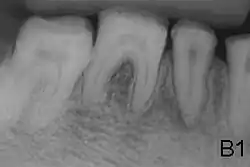

| Amelogenesis imperfecta, hypoplastic type. Note the association of pitted enamel and open bite. | |

- Enamel of abnormal thickness due to malfunction in enamel matrix formation. Enamel is very thin but hard & translucent, and may have random pits & grooves. Condition is of autosomal dominant, autosomal recessive, or x-linked pattern. Enamel differs in appearance from dentine radiographically as normal functional enamel.[20]

- Enamel has sound thickness, with a pitted appearance. It is less hard compared to normal enamel, and are prone to rapid wear, although not as intense as Type 3 AI. Condition is of autosomal dominant, autosomal recessive, or x-linked pattern. Enamel appears to be comparable to dentine in its radiodensity on radiographs.

- Enamel defect due to malfunction of enamel calcification, therefore enamel is of normal thickness but is extremely brittle, with an opaque/chalky presentation. Teeth are prone to staining and rapid wear, exposing dentine. Condition is of autosomal dominant and autosomal recessive pattern. Enamel appears less radioopaque compared to dentine on radiographs.